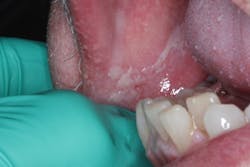

A 62-year-old male presents to the office with the chief complaint that for the last nine days, he has had a severe burning feeling on his tongue and the insides of his cheeks, accompanied by “white patches all over.” His health history includes recent dry mouth, type 2 diabetes, and high blood pressure. He takes blood pressure medication and shares that he has been undergoing changes to his diabetes prescriptions to gain better control of his sugar levels.

The patient indicates that the lesions initially appeared eight months ago and his MD told him to rinse with salt water. The lesions subsided, but recently came back, worse than before. He also complains of a fetid odor to his breath that seems to be exacerbated with this recent onslaught of lesions.

Clinical exam reveals white leukoplakic patches on the right and left lateral borders of the tongue and on the buccal mucosa throughout the oral cavity. A swipe with gauze removed the lesions.

Acute pseudomembranous candidiasis (thrush)

Candidiasis is an opportunistic fungal infection that presents primarily when there is compromise in the immune system of the host. Candida albicans is the most prevalent form of the eight species of Candida. It presents on the surface of the mucosa typically as white patches (may or may not rub off) or bright red inflamed tissue. Lesions associated with C. albicans include angular cheilitis (perleche), median rhomboid glossitis, and chronic mucocutaneous candidiasis. See the table below for the predisposing factors to Candidiasis1: